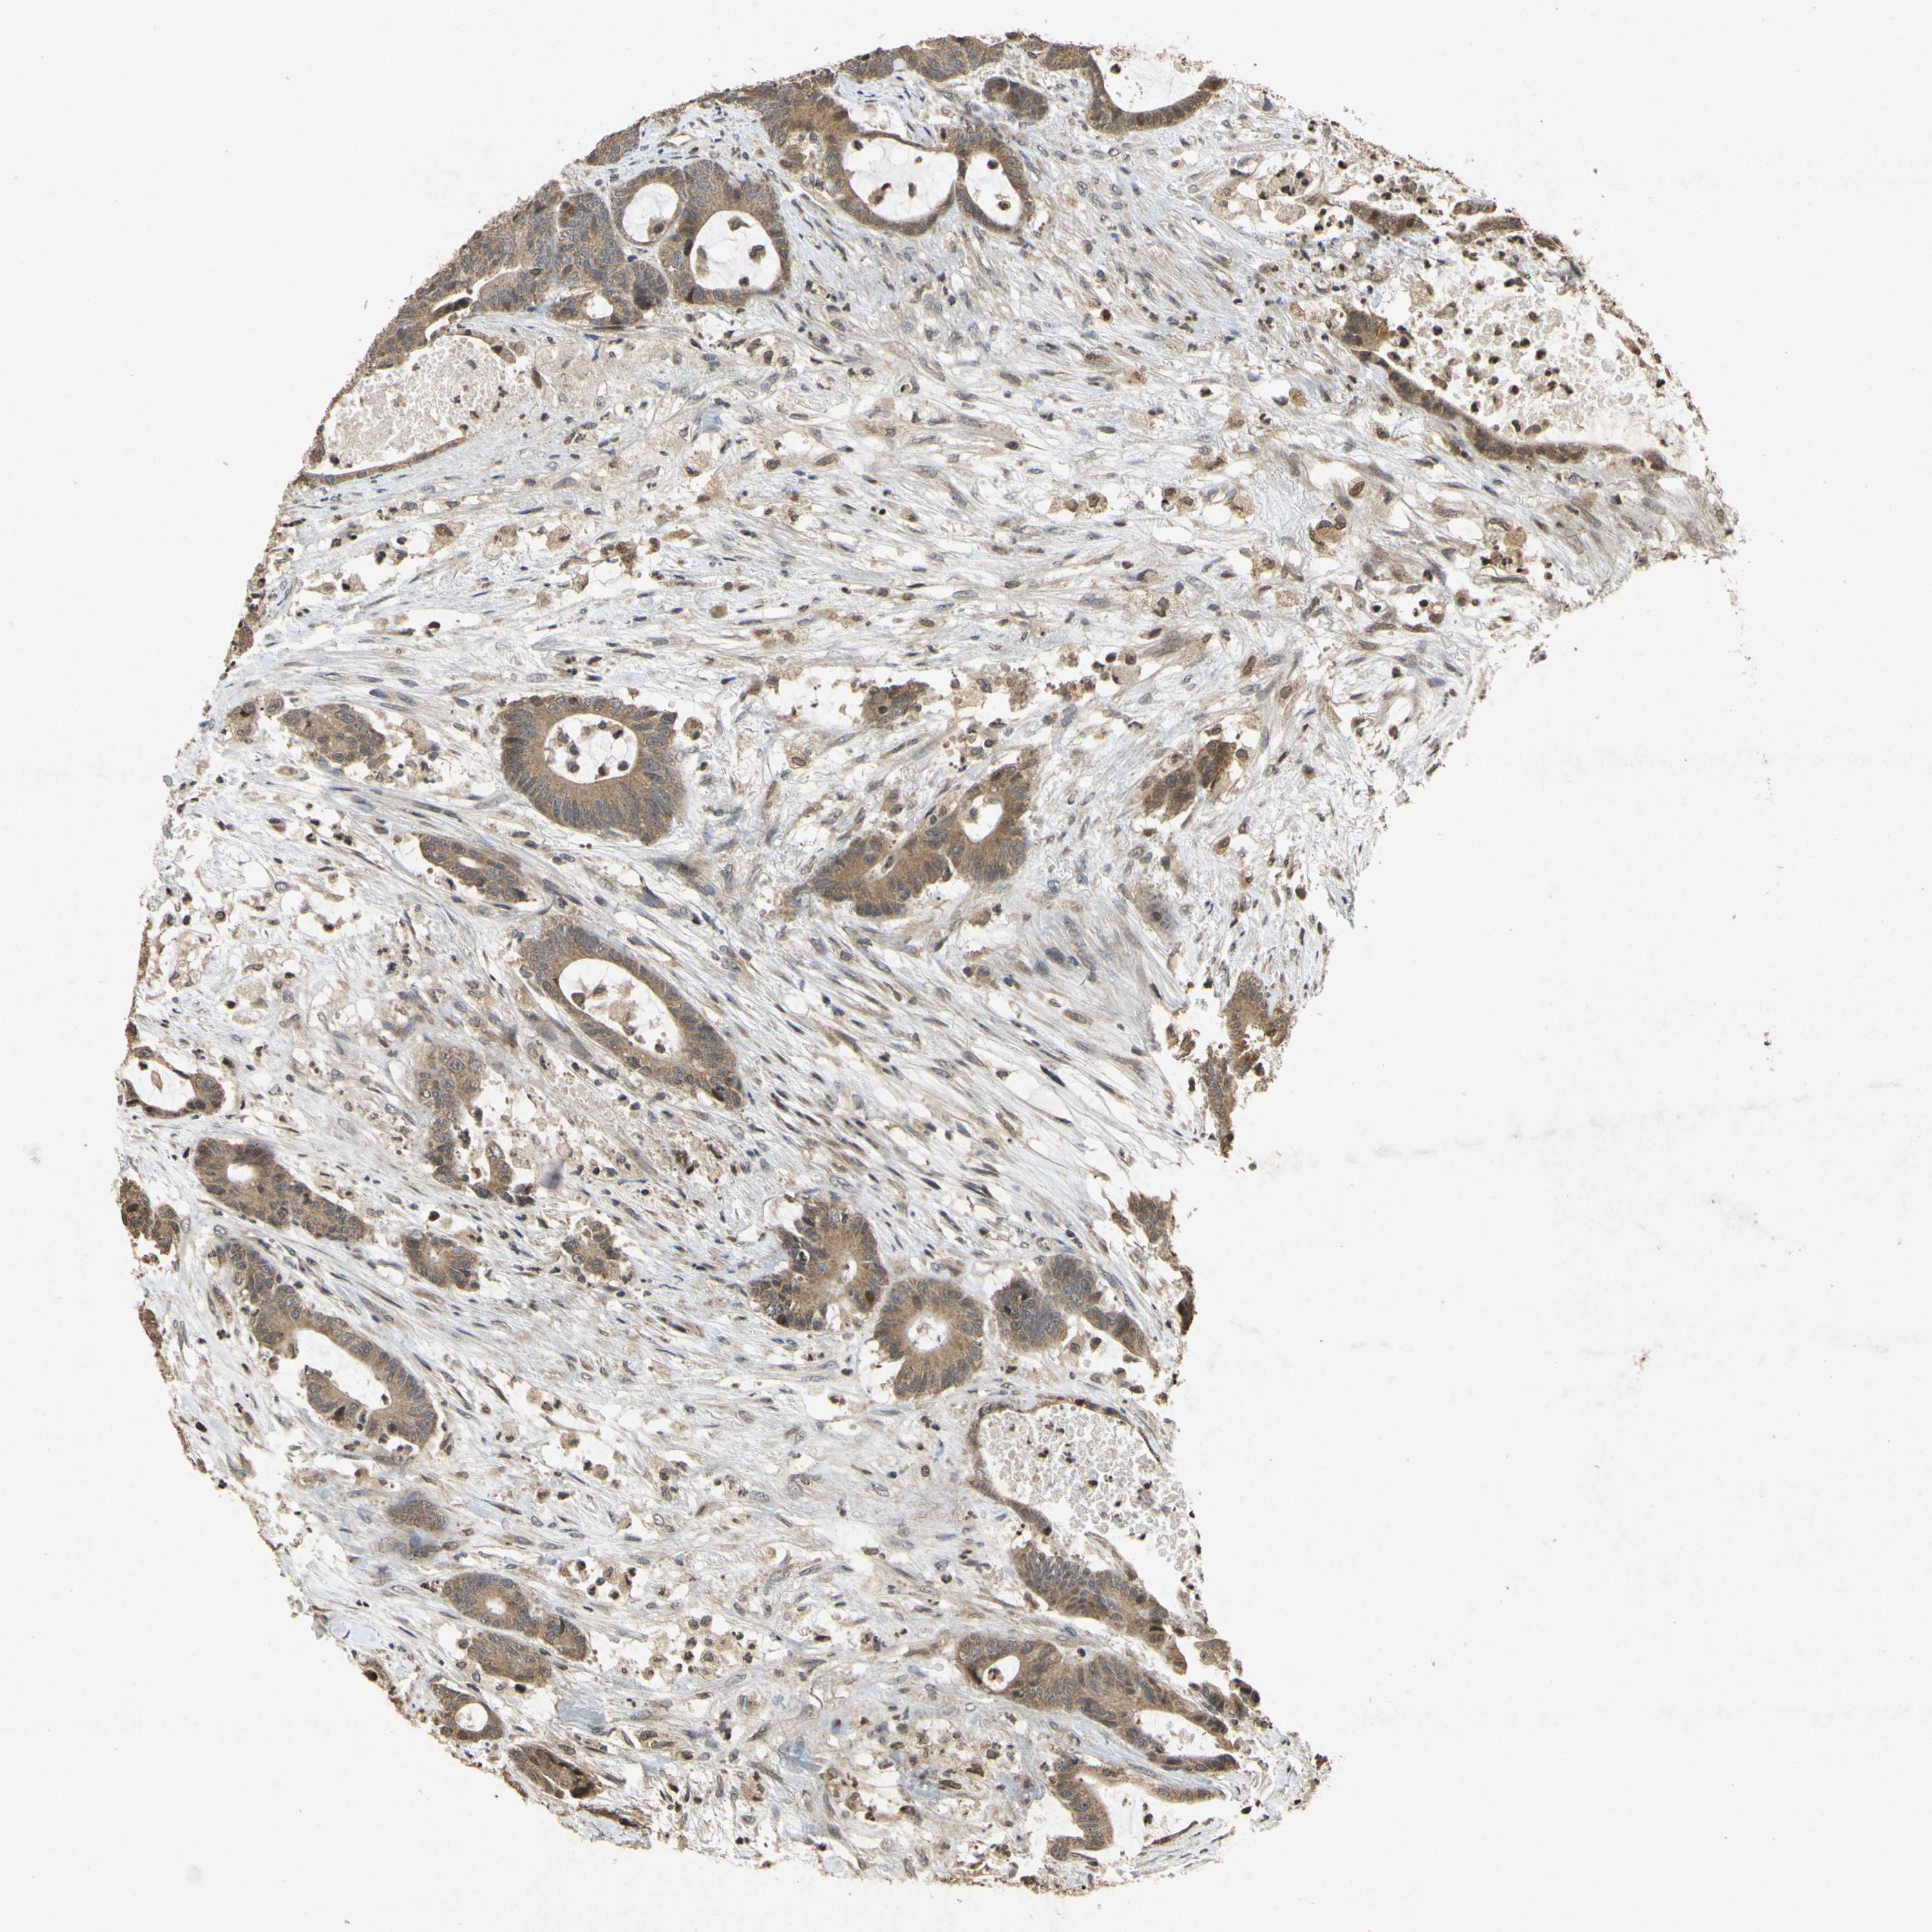

CANCER COLORECTAL CANCER Show tissue menu

Colorectal cancer

Human cancer

Colon adenocarcinoma